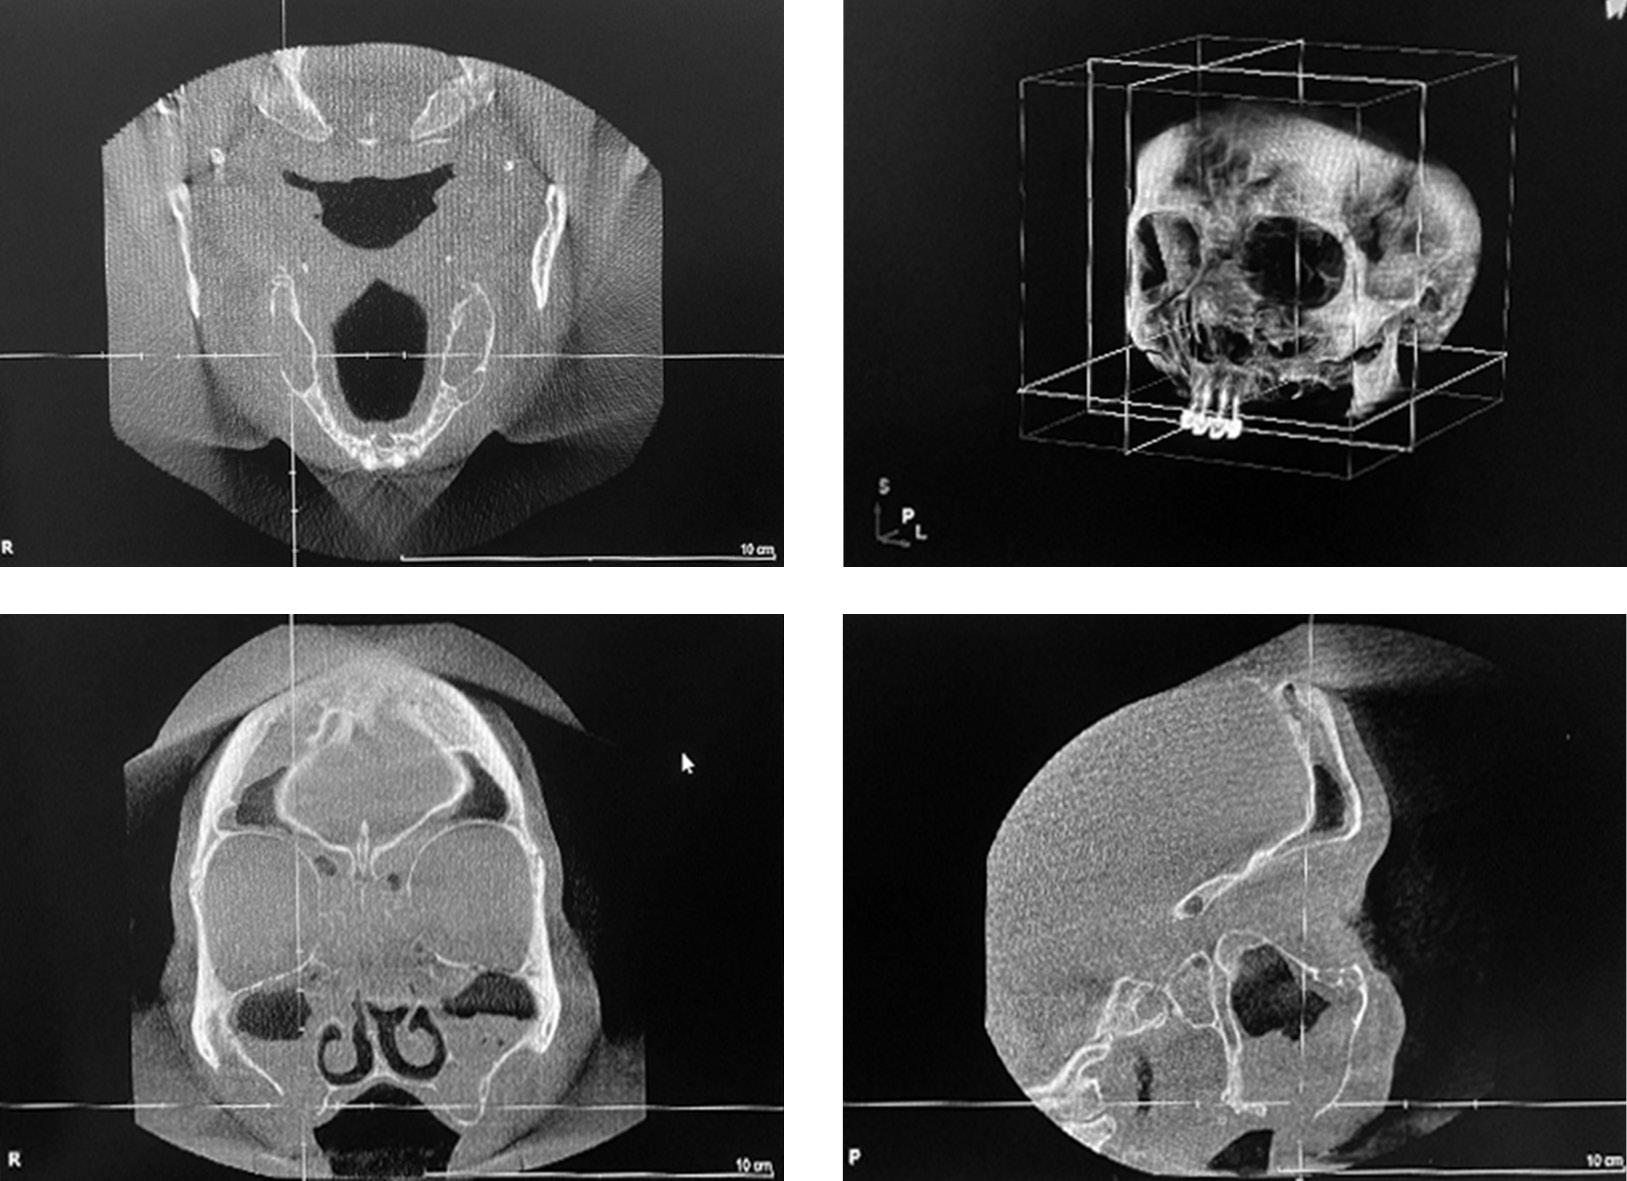

Patient A, 58 years old, was urgently admitted to the Clinic of Otolaryngology of the First Pavlov State Medical University of St. Petersburg with complaints of nasal congestion, difficulty nasal breathing, headache, sensation of pressure and fullness in the maxillary sinuses, and food and water leaking from mouth into the nose. Medical history revealed that the patient had teeth 1.4, 1.5, 1.6 removed approximately a year ago, after which acute right sinusitis developed and an oroantral communication formed. The patient had nasal breathing problems for the past 25 years. The patient had 3 episodes of right maxillary sinusitis within one year. The patient had an episode of severe stress and hypothermia one week prior to hospitalization. Cone beam computed tomography showed subtotal shadowing of both maxillary sinuses with an exudative component, total shadowing of the ethmoidal labyrinth cells, a defect in the right alveolar process of the upper jaw up to 10 mm in the projection of the missing teeth 1.5, 1.6 due to oroantral communication (Figure 3). Objective nasal examination revealed edematous and hyperemic mucosa, moderate bilateral mucopurulent discharge, deflected nasal septum, and a positive right nasal-oral test. After systemic antibacterial therapy and puncture, the acute inflammation was treated, but right oroantral communication and nasal breathing difficulties persisted. The patient underwent combined multidisciplinary treatment of the intranasal structures, including endoscopic septoplasty, endoscopic right maxillary antrostomy, and bilateral inferior vasotomy by an otolaryngologist and plastic surgery of the oroantral fistula by an oral surgeon to restore nasal breathing, improve sinus aerodynamics, and adequately eliminate the stomatogenic source of infection. After 7 days, a follow-up cone beam computed tomography of the sinuses and maxillofacial region showed complete restoration of airiness in both maxillary sinuses (Figure 4). Objectively, the patient reported improved nasal breathing, pain relief, and no communication between the sinuses and oral cavity.

Fig. 3. Cone beam computed tomography: subtotal shadowing of both maxillary sinuses with an exudative component, total shadowing of the ethmoidal labyrinth cells, a defect in the right alveolar process of the upper jaw up to 10 mm in the projection of the missing teeth 1.5, 1.6 (oroantral communication)

Рис. 3. Конусно-лучевая компьютерная томография: субтотальное затенение обеих верхнечелюстных пазух с наличием экссудативного компонента, тотальное затенение клеток решетчатого лабиринта, дефект альвеолярного отростка верхней челюсти справа до 10 мм в проекции отсутствующих зубов 1.5, 1.6 (ороантральное сообщение)